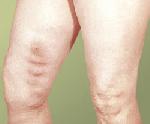

Варикозное расширение вен — стойкое и необратимое их расширение и удлинение, возникающее в результате грубых патологических изменений стенки вен, а также недостаточности их клапанного аппарата вследствие генетического дефекта.

Различают тромбофлебиты поверхностных, часто варикозно изменённых ( Варикозное расширение вен), и глубоких вен; особенно часто поражаются вены нижних конечностей и малого таза, реже — полые, воротная, печёночные.